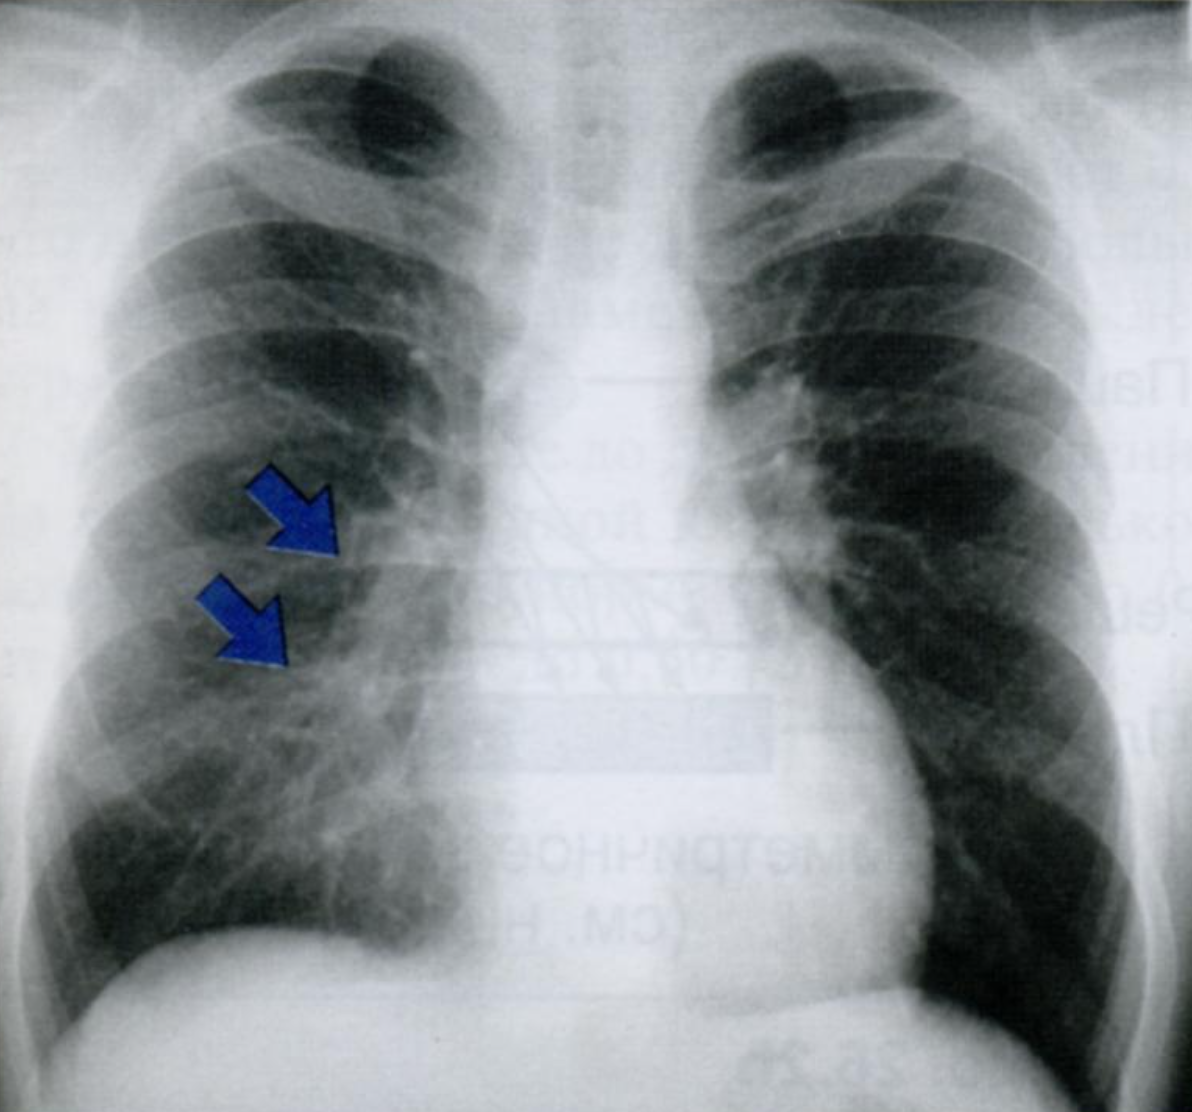

На снимке в правом легочном поле мы видем участок инфильтрации. Справа легкое имеет три доли. В данную проекцию попадают СД и НД. В какой из них расположена инфильтрация и почему Вы пришли к такому выводу?

Запомните: если на фоне измененного легочного рисунка виден силуэт сердечной тени - затенение распологается в заднем отделе НД, а если силуэт не определяется - в переднем отделе СД.

КТ на уровне правого предсердия (2), с инфильтрацией (37) в СД (33), которая соприкасается с ПП (2).

Инфильтрация и окружающих отек повышают плотность легочной ткани до плотности, эквивалентной сердечной тени.

В результате граница между инфильтратом и контуром сердца не визуализируется.

Ответ: инфильтрат раполается в переднем отделе СД правого легкого.